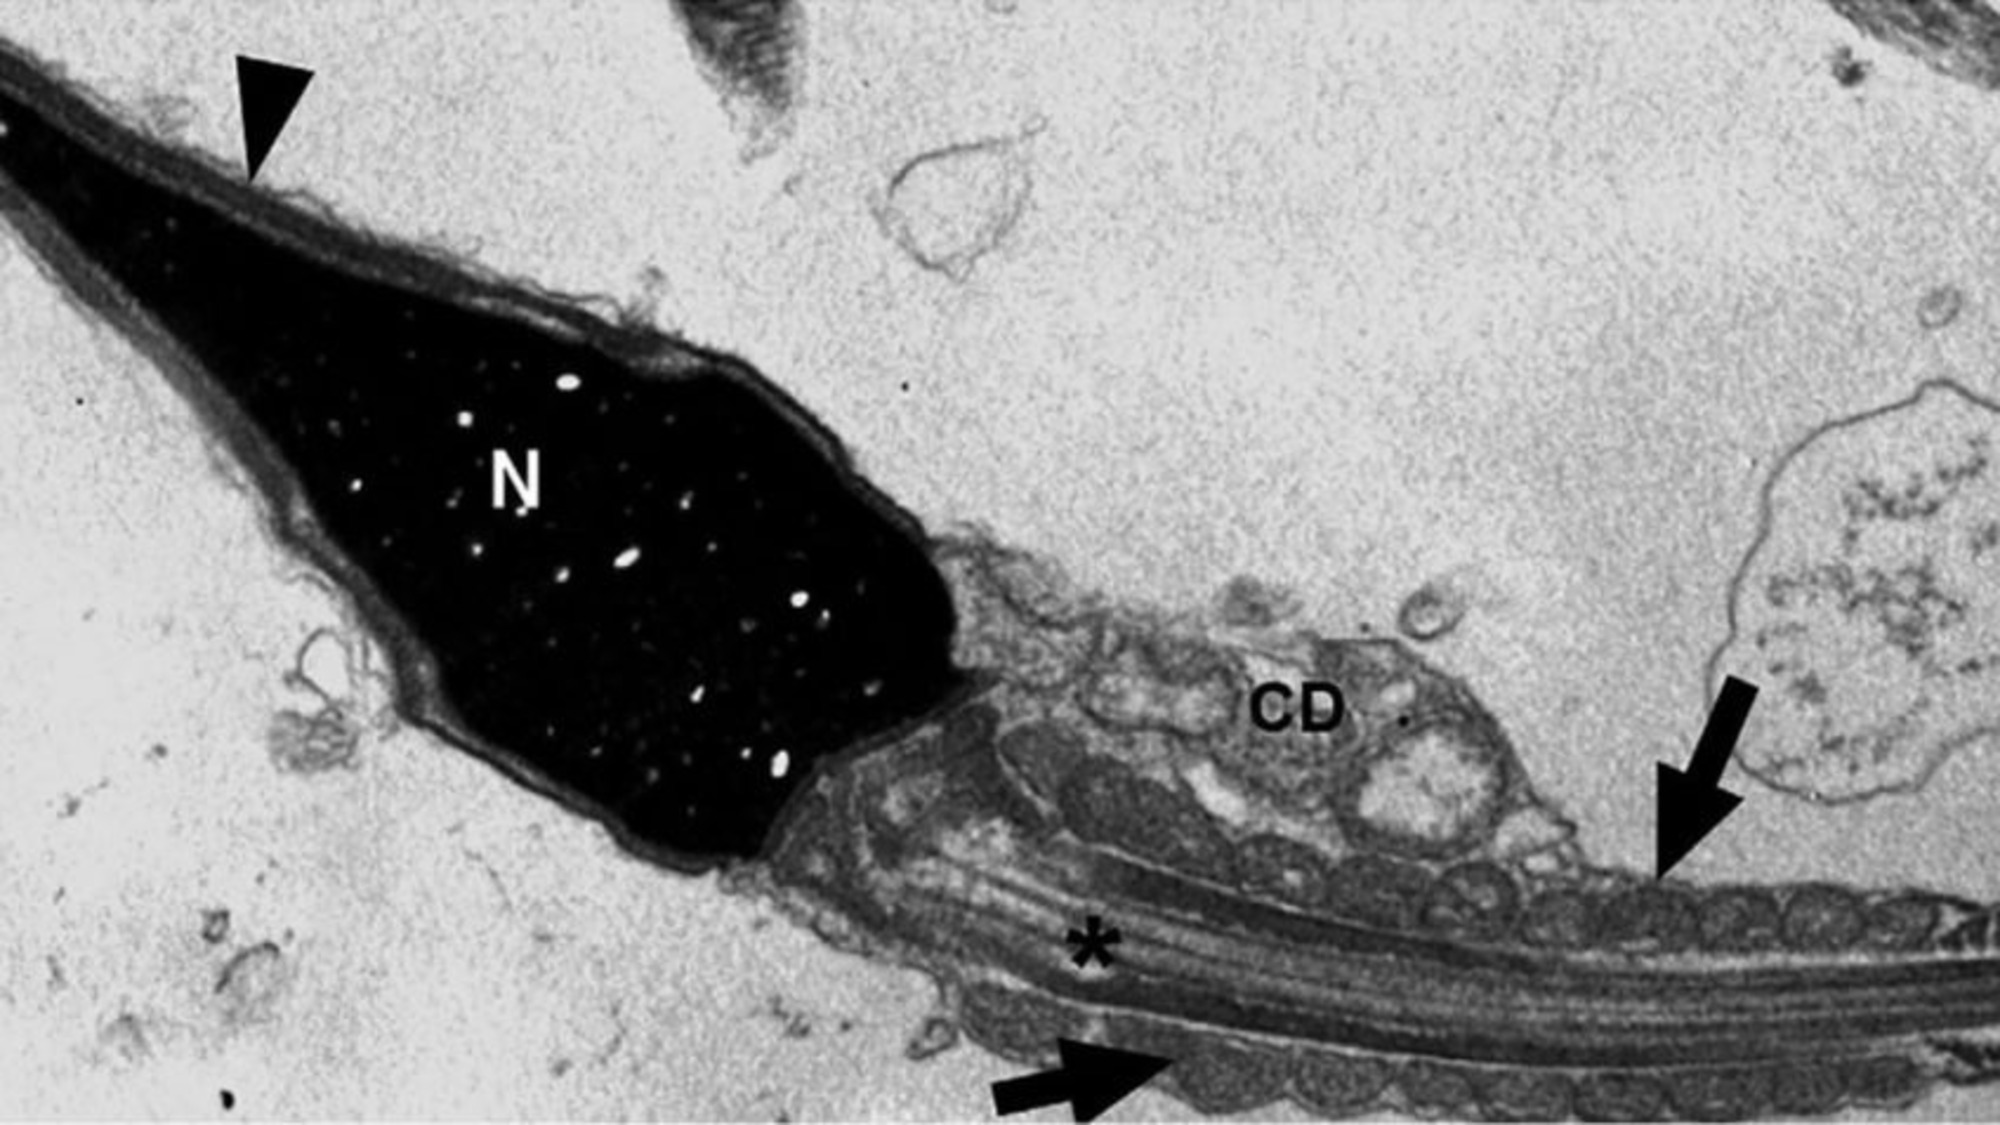

Covid pode permanecer no espermatozoide por até 110 dias após infecção | Foto: Imagem: Reprodução

Mecanismo Imunológico: Os espermatozoides mostraram produzir “armadilhas extracelulares” baseadas em DNA para neutralizar o vírus, uma função imunológica inédita para essas células.